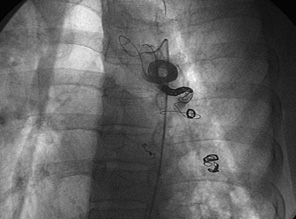

肺がんと喀血・関連動画